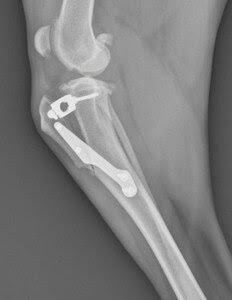

Below is the post operative TTA x-ray:

In 2005, a procedure known as the Tibial Tuberosity Advancement (TTA) was developed where the top part of the tibia, called the tibial tuberosity, is cut and advanced forward. The result is two fold:

1.) The advancement increases tension on the very thick and strong patellar tendon that runs over the knee cap and inserts at the head of the tibia. This increased tension on the patellar tendon stops the sheer force created by the CCL tear.

2.) The advancement of the tibial tuberosity lengthens the patellar tendon thereby decreasing its angle relative to the tibial slope. The result is that the deep tibial slope angles are functionally reduced without the necessity to change the angle by cutting such a large wedge of bone as is the case with TPLO. Overall, TTA was considered by many veterinary surgeons to be less invasive and found that patients were quicker to weight bearing and experienced less complications. What’s more, the procedure had a shorter learning curve than TPLO, so veterinarians without residency training were able to quickly gain proficiency with the procedure.